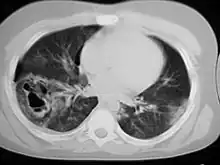

| A CT scan showing a pulmonary contusion (red arrow) accompanied by a rib fracture (purple arrow) | |

Computed tomography

Computed tomography (CT scanning) is a more sensitive test for pulmonary contusion,[6][33] and it can identify abdominal, chest, or other injuries that accompany the contusion.[38] In one study, chest X-ray detected pulmonary contusions in 16.3% of people with serious blunt trauma, while CT detected them in 31.2% of the same people.[45] Unlike X-ray, CT scanning can detect the contusion almost immediately after the injury.[43] However, in both X-ray and CT a contusion may become more visible over the first 24–48 hours after trauma as bleeding and edema into lung tissues progress.[46] CT scanning also helps determine the size of a contusion, which is useful in determining whether a patient needs mechanical ventilation; a larger volume of contused lung on CT scan is associated with an increased likelihood that ventilation will be needed.[43] CT scans also help differentiate between contusion and pulmonary hematoma, which may be difficult to tell apart otherwise.[47] However, pulmonary contusions that are visible on CT but not chest X-ray are usually not severe enough to affect outcome or treatment.[37]